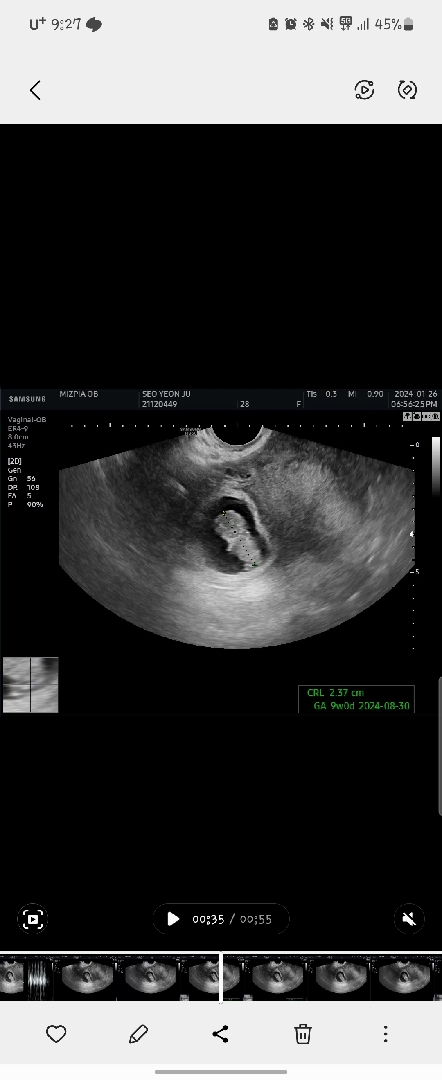

9주차 초음파보고왔어요!!!

9주6일차인데 오늘가보니 9주0일차정도라구 하시네요~~저번초음파때는 8일정도차이났었는데 오차범위가 좀줄어들어서 넘 기분좋았지모에요~~~ 9주차 초음파여서 처음으로 배초음파 시도했는데 뭐때문인진몰라도 잘안보여서 질초음파했어요!!! 보통 9주정도면 배초음파 하신다고들 하시던데ㅠㅠ 제가 살이많아서 그런가 부끄러어여...ㅎㅎ 암튼 이등신 젤리곰보고왔더니 기분이 좋네요!! 남편은 초음파보면서 ㄱㅖ속대두라고 깔깔웃고있어요 ㅋㅋㅋ이런게 가족인가요~~ㅋㅋㅋ